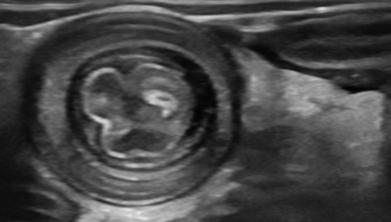

典型超声表现

· “靶环征”或“同心圆”:在横断面上看到像靶子一样的圆圈,这是肠子套叠的标志性图像。

图片2.jpg

· “假肾征”:在纵切面看起来像一个肾脏的图像,也是常见表现。